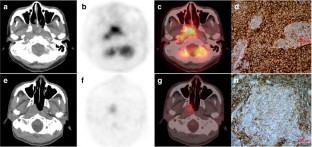

Fig. 1

Fig. 2